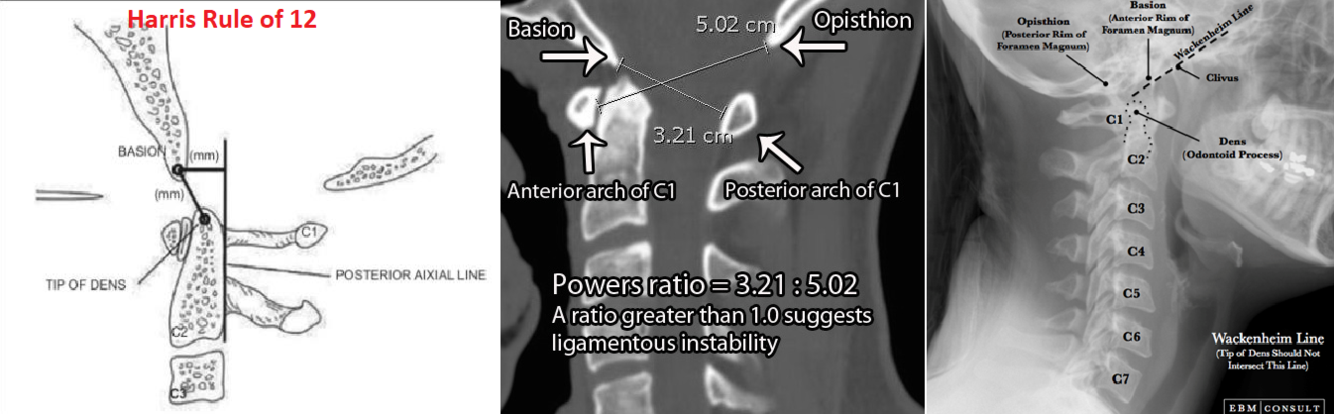

What are the radiographic parameters to be assessed on plain film for craniocervical dissociation?

What are the radiographic parameters to assess for atlas fractures?

What are the radiographic parameters to assess for atlantoaxial instability?